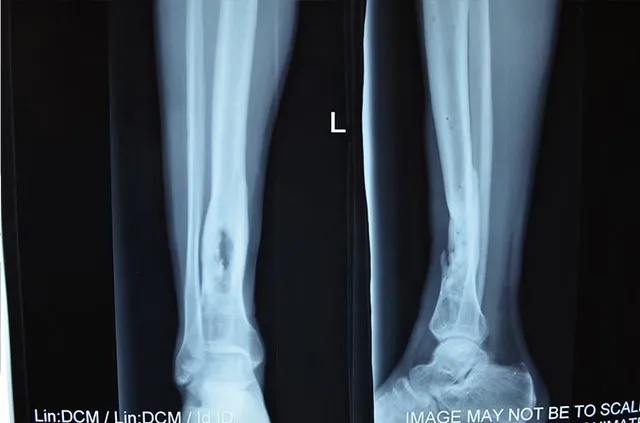

Поранений: Богдан З., 22 роки, боєць 17 ОМБР (54 ОМБр), поранений біля с. Попасна. Травма: Ліва нога: дірчастий дефект лівої великогомілкової кістки на межі середньої нижньої третини, больовий синдром.

Богдан отримав поранення півтора роки тому, переніс кілька операцій. І хоча кістка частково зрослася, у ній залишається великий отвір – дірчастий дефект, через який кістка дуже крихка, а пересування викликає сильні болі. Боєць не може повноцінно навантажувати ногу. Подібні дефекти кісткової тканини організм не може відновити самостійно, тому у будь-який час кістка може знову зламатися, або поступово деформуватися, що спричинить інвалідність.